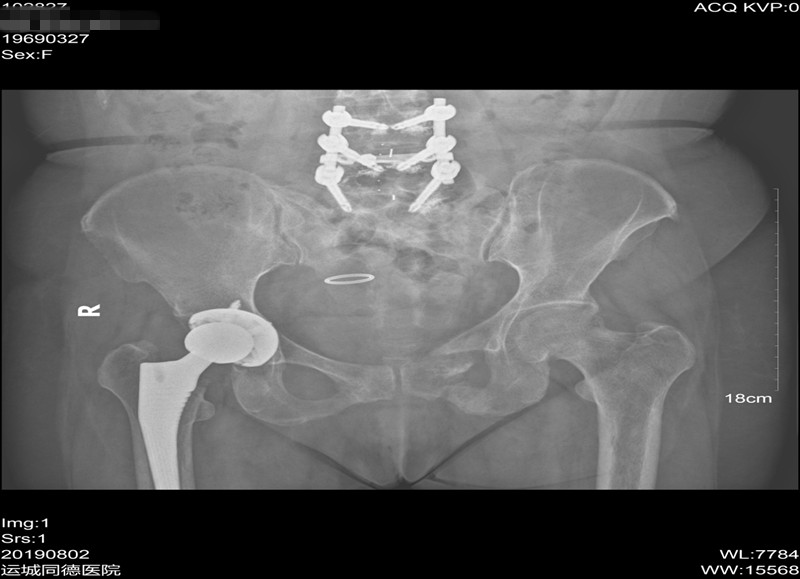

辅助检查:我院全身ECT骨显像+断层:双侧多根肋骨、第7、8、10、11、12胸椎、第1腰椎、左侧耻骨支、坐骨支、耻骨联合、双侧肩关节、肘关节、腕关节、骶髂关节、髋关节、踝关节可见多处放射性浓聚CT定位相可见多处肋骨、肋软骨连接处假骨折。胸腰椎正侧位片示:胸腰段骨质密度减低,骨皮质变薄或皮质线不连续,腰3-5椎体术后改变。骨盆前后位片示:左侧耻骨上下肢骨折,左股骨干上缘外侧皮质刀割样假骨折,右髋关节置换术后改变,腰椎内固定术后改变,右侧耻骨下支骨折。双髋关节CT示:左侧耻骨上下支骨折畸形愈合,右侧耻骨下支骨折,骶骨、左侧股骨颈陈旧骨折改变,右髋关节置换术后改变。曾行全身PET未发现肿瘤。

▼ 骨盆前后位片: